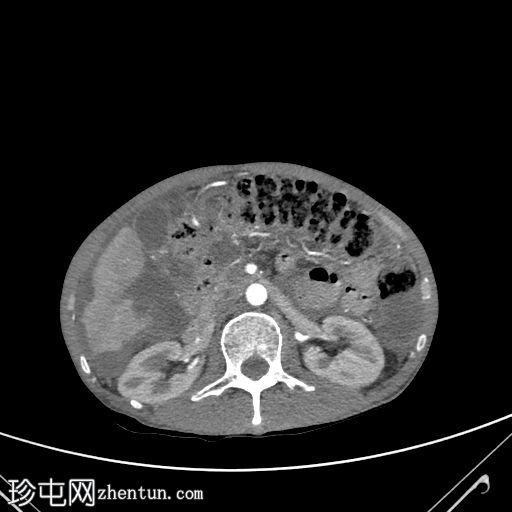

轴位增强扫描(门静脉期)

大网膜和肠系膜内可见低密度、不均匀的腹膜积液,脏器表面呈扇形凹陷,尤其以肝脏和脾脏最为明显。

阑尾肿大,长 5.0 cm,直径 1.2 cm,大小符合,可能提示阑尾黏液性肿瘤